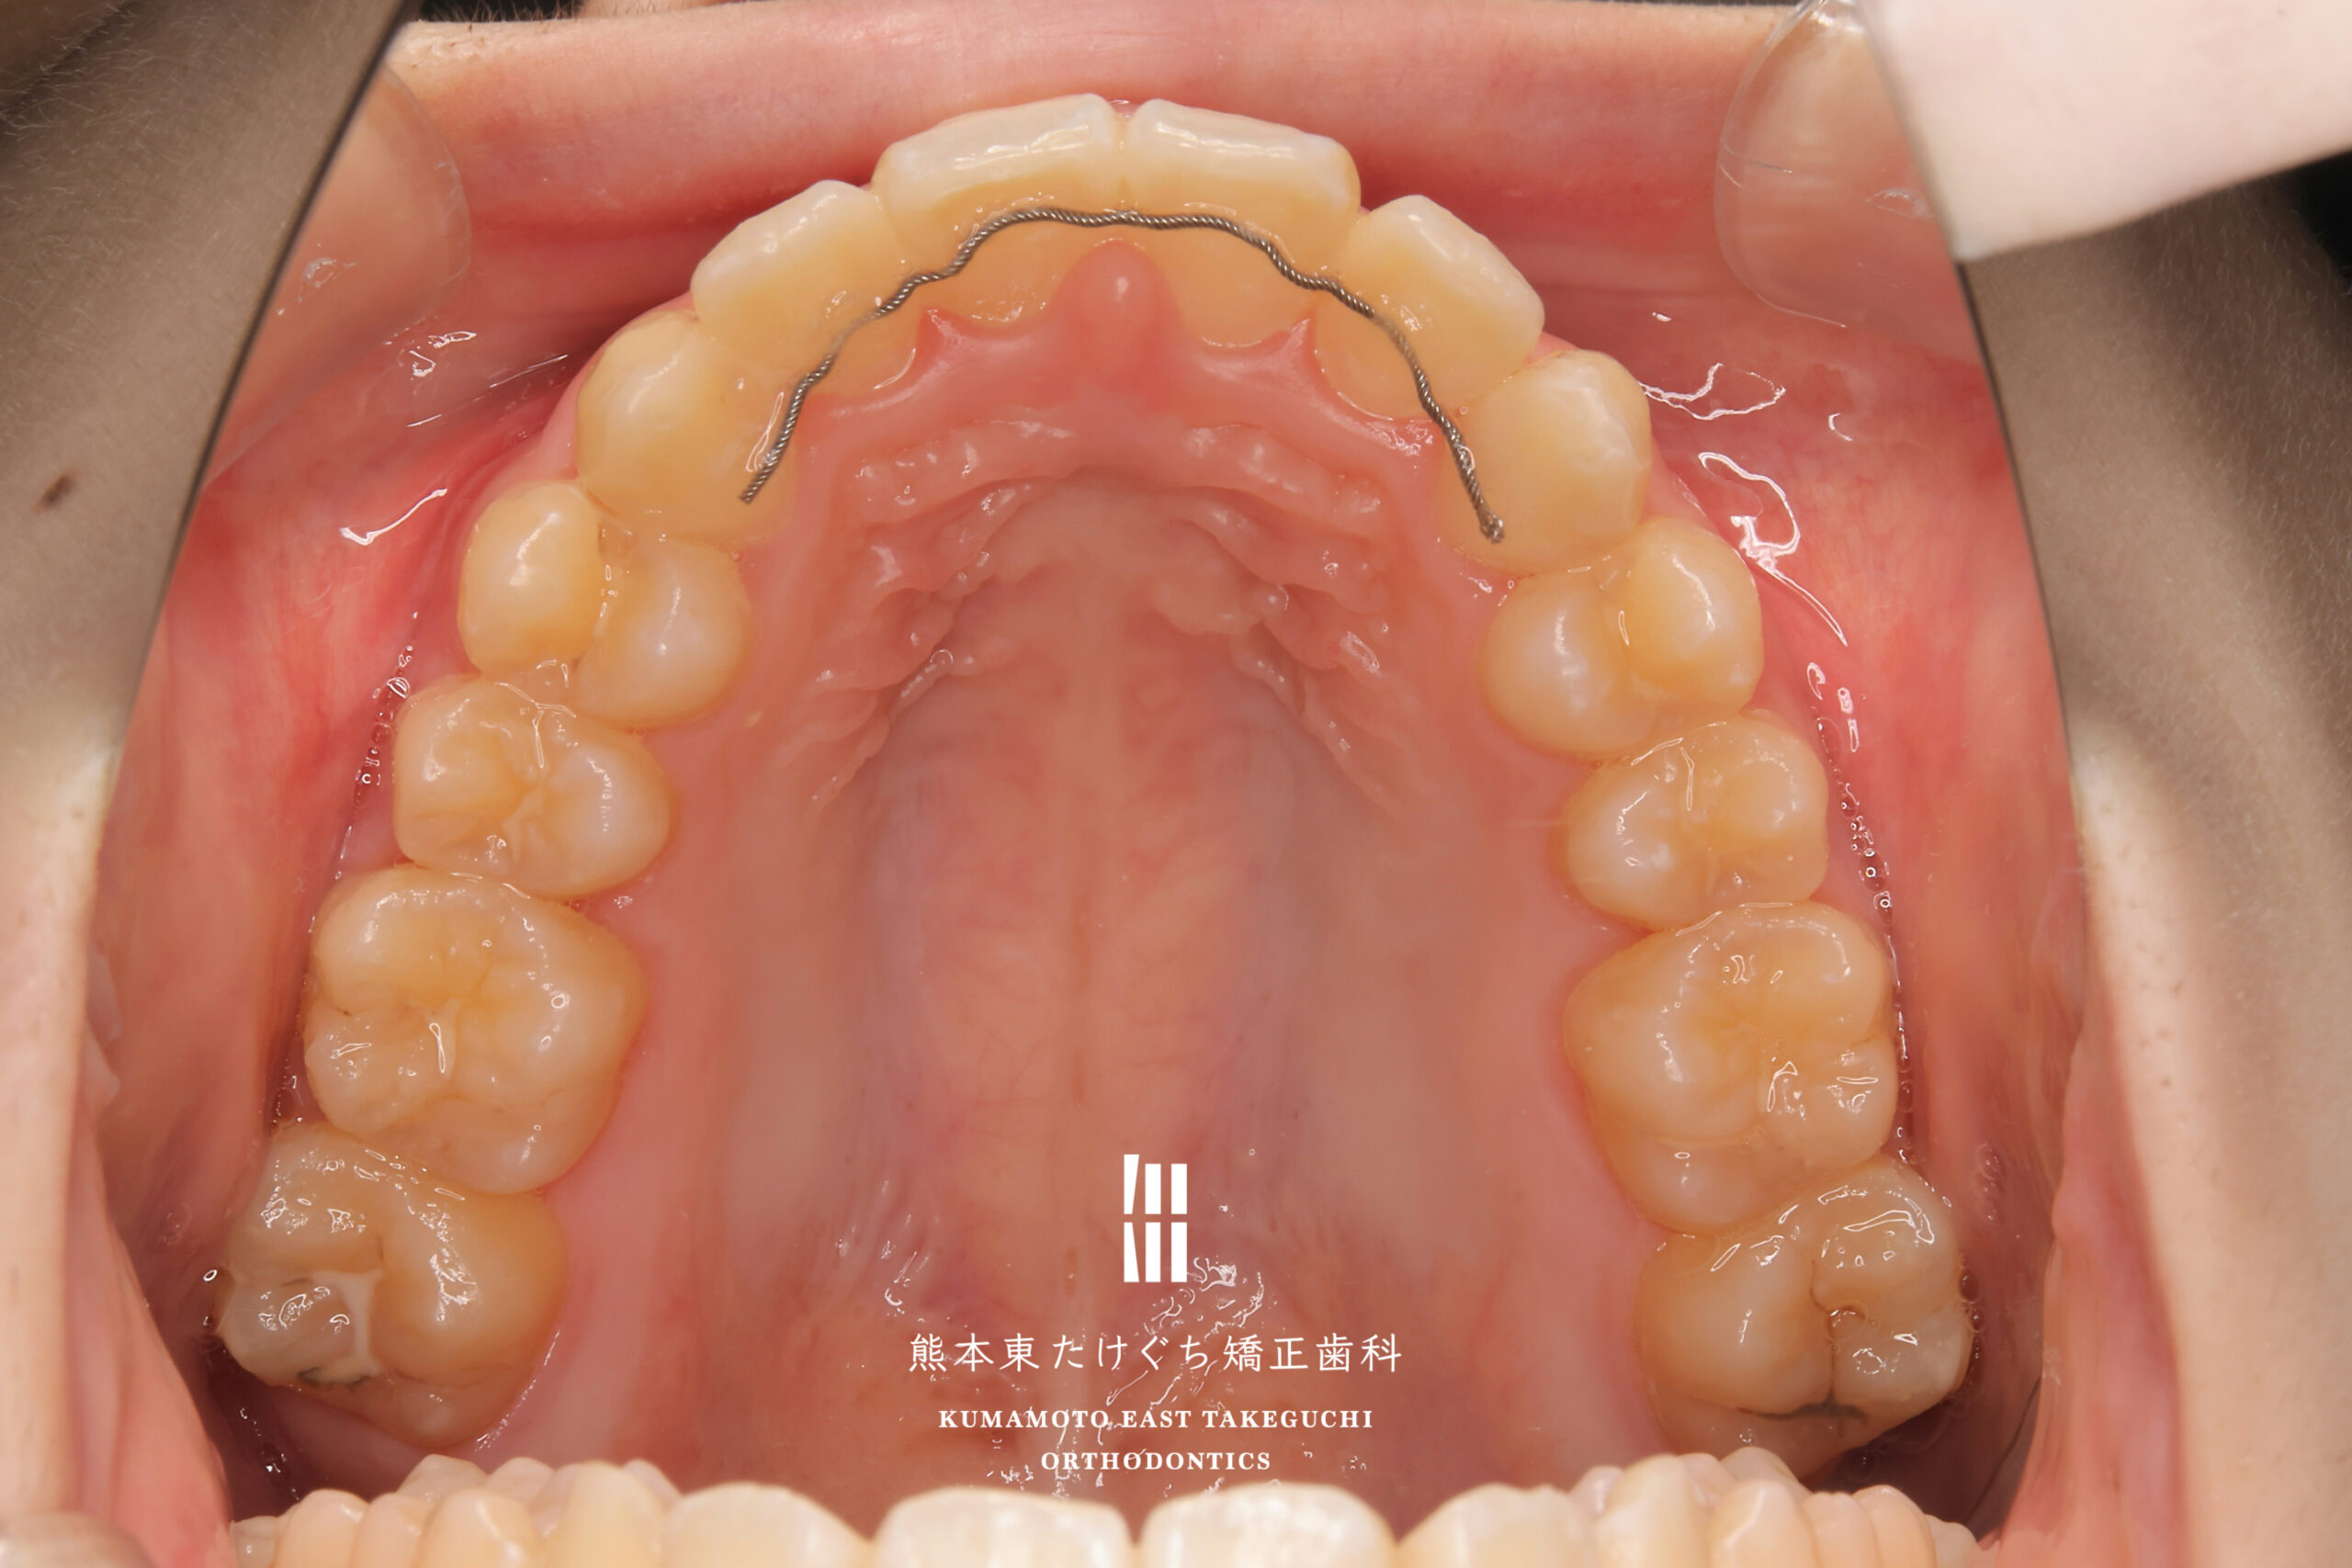

15歳女性 成人矯正 正中離開 出っ歯

治療内容 正中離開を伴う上顎前突を改善するため、非抜歯で固定式ワイヤーおよびディスタライザー(カリエールモーション)装置を用いて治療しました。